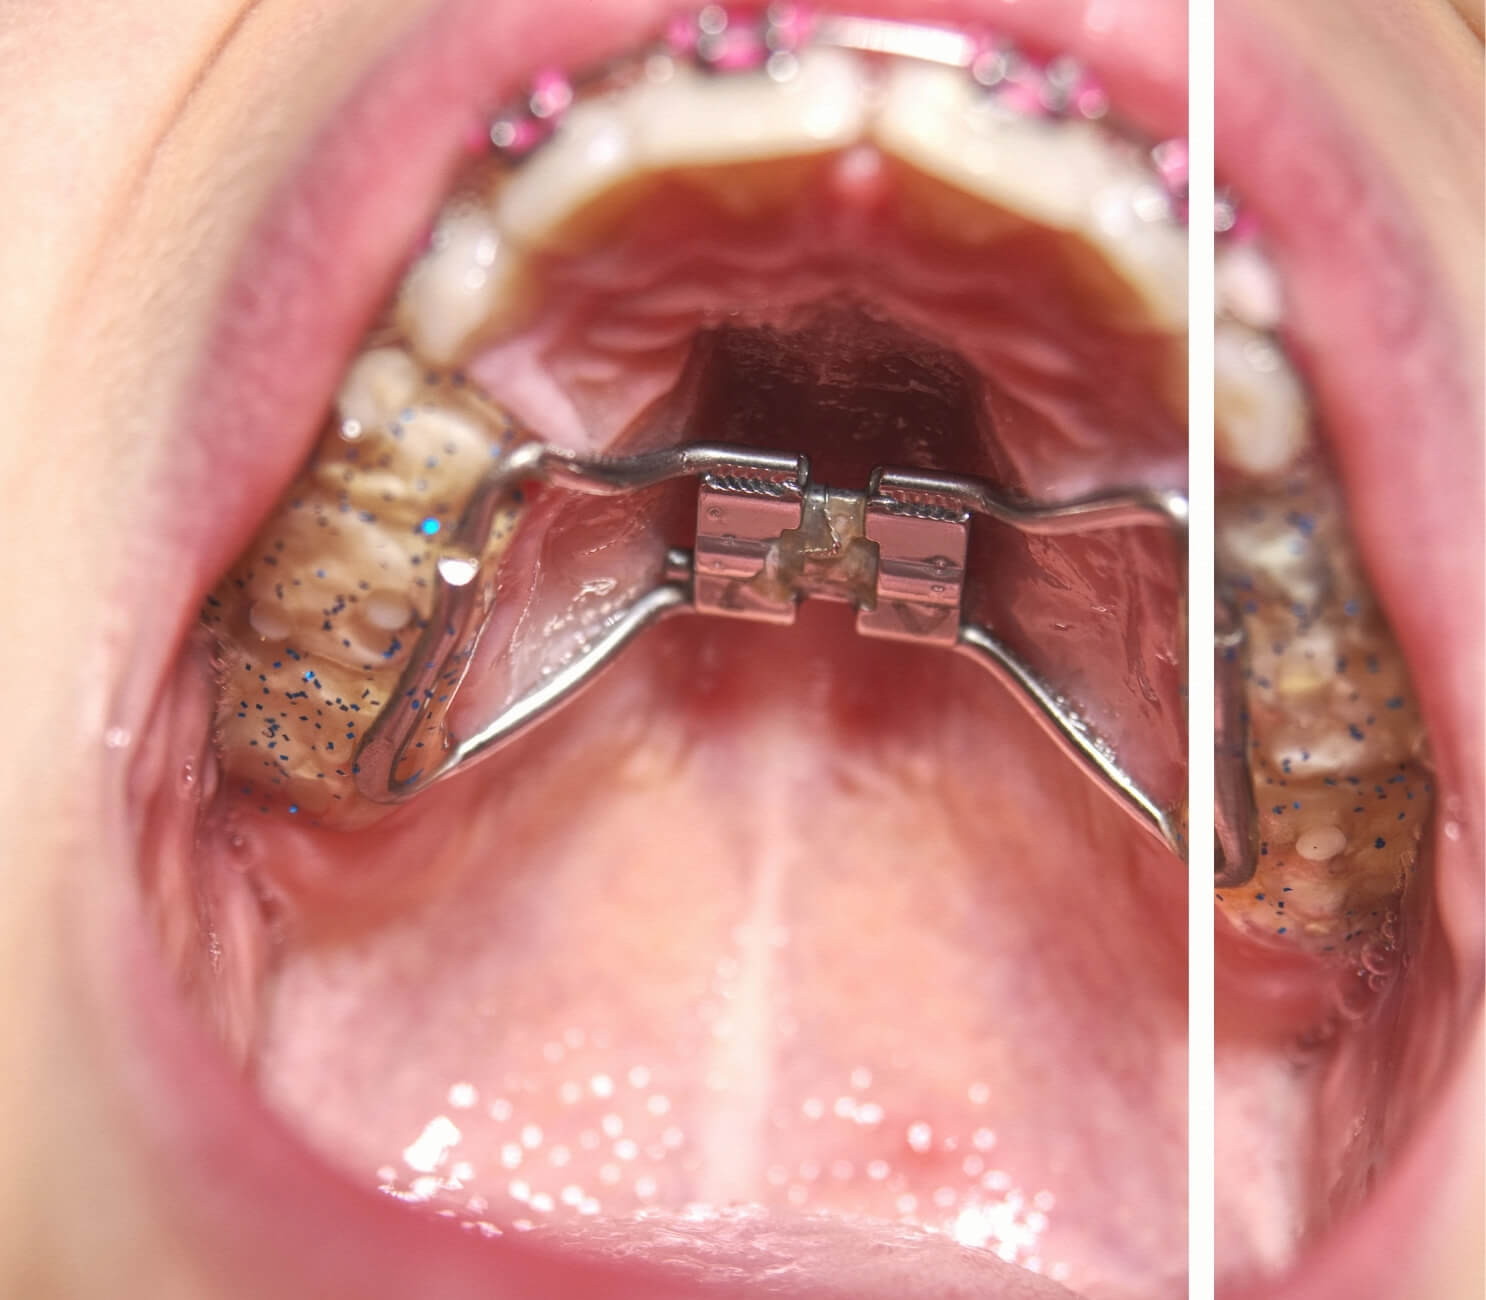

Geleneksel Hızlı Üst Çene Genişletme (RPE / Hyrax)

Çocuklarda ve büyüme dönemindeki ergenlerde üst damak suturü henüz açık olduğu için cerrahi destek olmadan doğrudan uygulanan klasik genişletme yöntemidir. RPE (Rapid Palatal Expansion) veya Hyrax apareyi olarak da bilinir. Aparey azı dişlerine sabitlenir ve genişletme kuvveti dişler üzerinden iletilir.Avantajları:- Mini vida gerektirmez, lokal anestezi uygulaması yoktur.

- Çocuk ve büyüme dönemindeki ergenlerde son derece etkili sonuç verir.

- Maliyet açısından MARPE’ye göre uygundur.

- Klinik olarak çok iyi anlaşılmış, uzun yıllardır uygulanan bir yöntemdir.

- Yalnızca büyüme dönemindeki hastalarda etkilidir (genellikle 7-14 yaş).

- Sutur olgunlaşması ileri seviyedeki yetişkinlerde dişlerin devrilmesine yol açabilir, gerçek iskeletsel genişleme sağlanamayabilir.

- Geç ergenlik ve genç yetişkinlerde MARPE veya SARPE daha güvenilir sonuç verir.